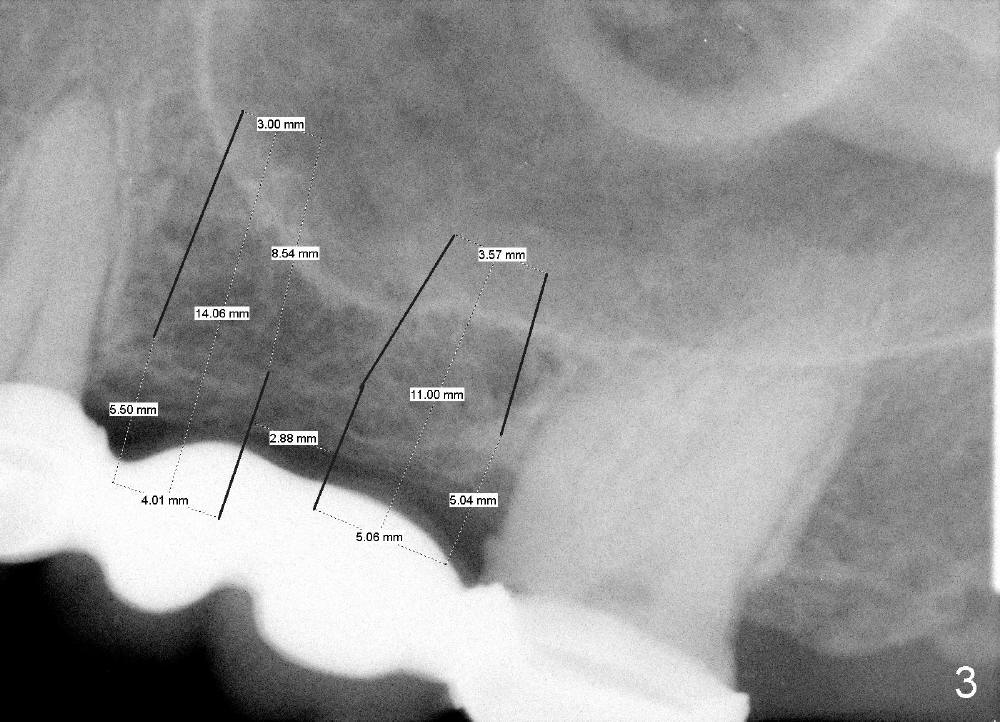

A 54-year-old lady has severe toothache in the upper left region. Exam reveals a posterior 4-unit bridge (Fig.1 B); one of the abutments (#15) needs root canal therapy (RCT, Fig.2). The bridge is temporarily recemented after RCT. Two implants are planned (4x14 mm and 5x11 mm at the sites of #13 and 14) with sinus lift/graft (Fig.3).